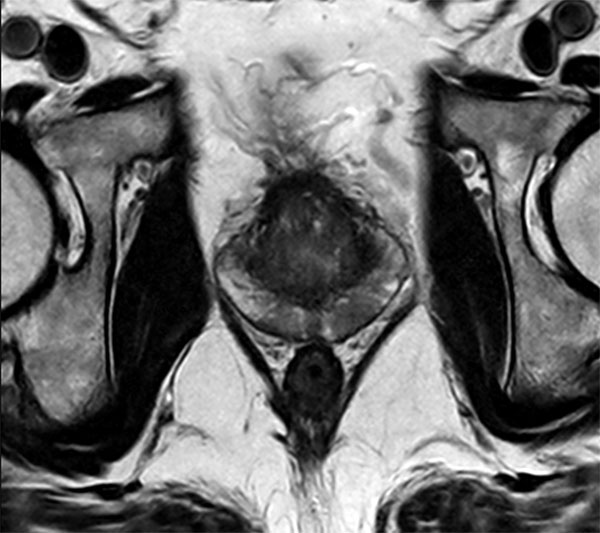

Axial T2w TSE